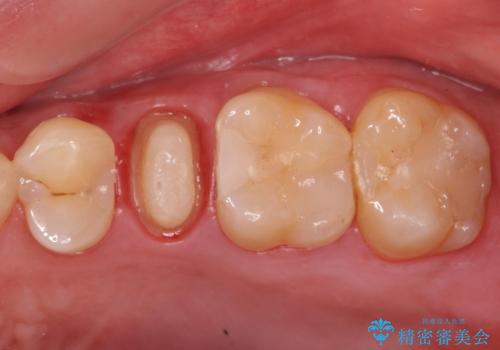

- 左上の歯茎にできものができたとのことで来院された患者様です。

術前検査より根管内の感染が疑われたため、再根管治療を行います。

根管内の感染源を可能な限り除去し洗浄しました。